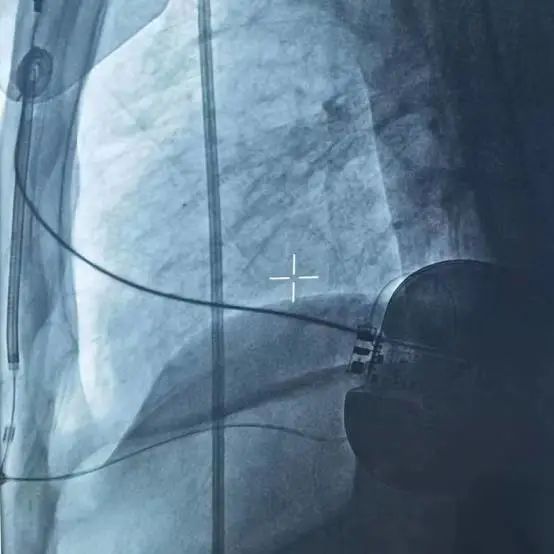

手术在全身麻醉下进行,常规消毒、铺巾,取左腋中线平等第5-6肋为预定点,切开一长约5cm切口,逐层分离至深筋膜,分离囊袋至背阔肌与前锯肌之间。再于胸骨左缘1cm为预定点,切开一长约3cm切口,逐层分离至深筋膜层,预埋两根缝合线,用引导针,于切口间建立隧道,后引导除颤电极于皮下,固定除颤电极。于胸骨柄上缘(距下切口14cm处)为预定点,切开一长约2cm切口,逐层分离至深筋膜层,用导引针导引除颤电极于深筋膜层至上切口位置,固定电极头端,连接脉冲发生器(S-ICD 209),固定脉冲发生器于深筋膜层,排除空气后关闭皮下组织。进行除颤阈值测试,采用50HZ,200MA交流电方式进行诱颤,S-ICD正确识别,经首次65J除颤成功,除颤阻抗74Ω。缝合皮肤,术区纱布覆盖,包扎,弹力绷带加压包扎止血。手术圆满成功,耗时约1小时。送病人回病房。

(除颤阈值测试报告)

(术后影像)